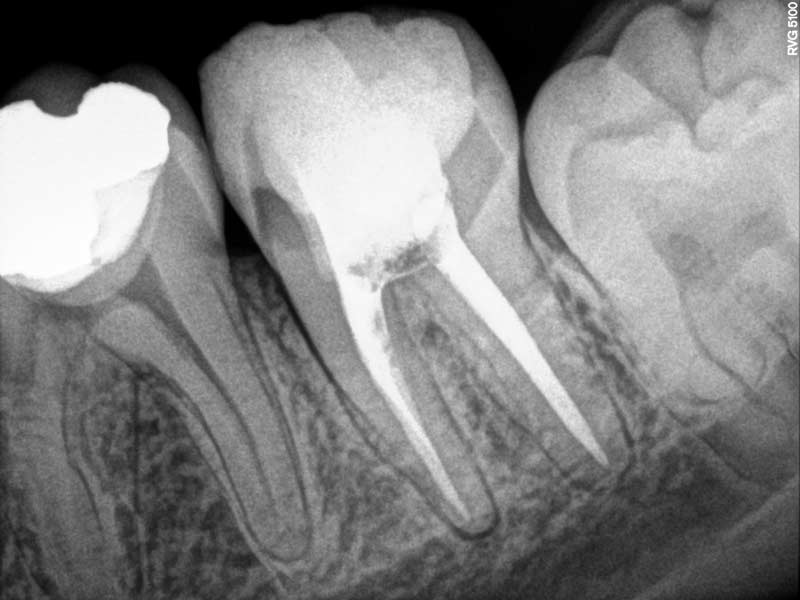

Retratamiento de conducto

Estas radiografías pertenecen a una paciente que tuvo que realizarse un retratamiento de conducto.